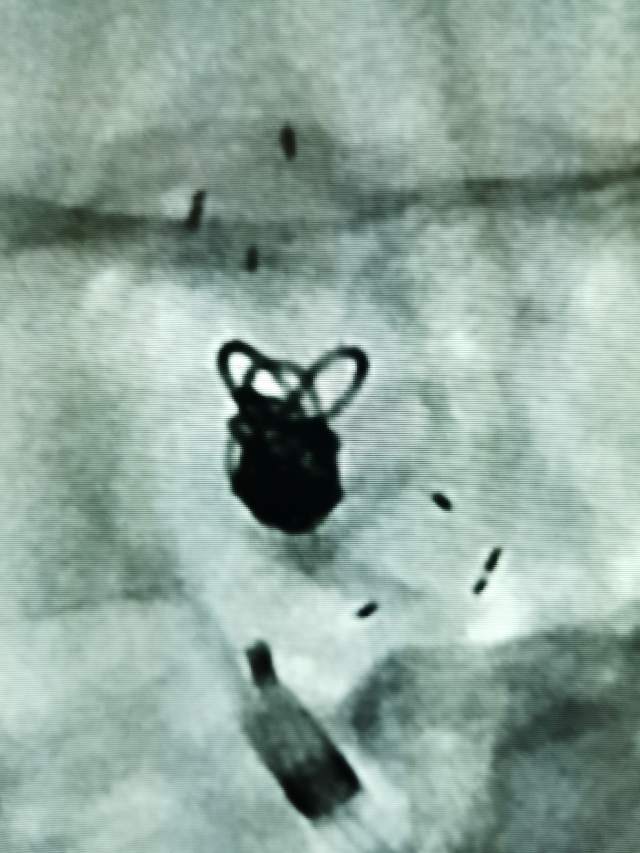

Jailing技术治疗床突旁未破裂动脉瘤